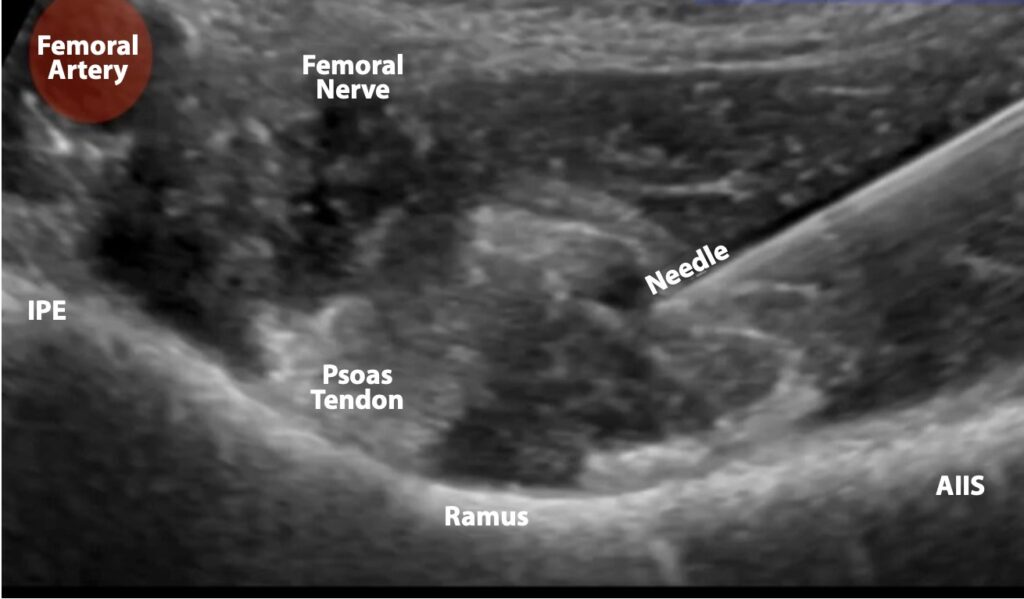

Figure 7. Ultrasound image demonstrating needle approach. Note how the needle is seen in-plane, approaching the psoas tendon. The femoral artery and femoral nerves are clearly seen and avoided.

- Advance the needle under direct visualization to the psoas muscle. Use an in-plane approach, moving from lateral to medial until contact with the ilium is made under the psoas tendon (figures 3,4,5).

- Once on the fascia investing the bone beneath the psoas tendon, spin the needle to help ensure the needle cuts below fascia.